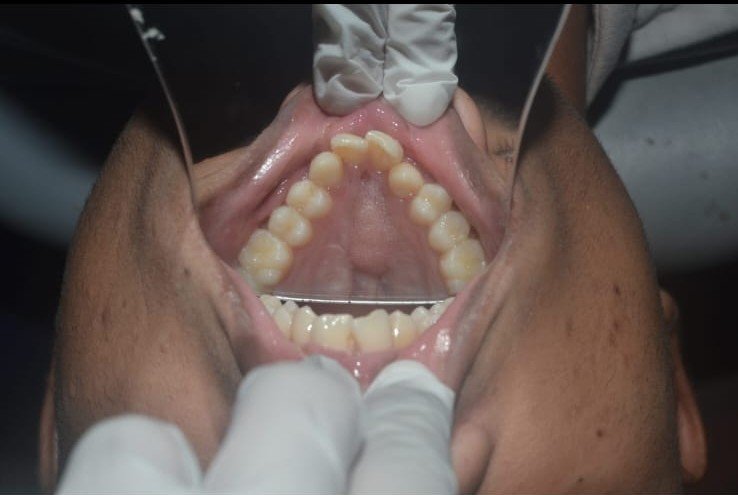

Maxillary prognathism is a dental and facial condition in which the upper jaw extends forward more than normal in relation to the lower jaw. This condition can affect the overall balance of the face and may lead to difficulties with proper bite alignment, chewing, and speech. In many cases, maxillary prognathism develops due to genetic factors, abnormal jaw growth, or developmental conditions that affect the structure of the facial bones.

- Constricted arch.